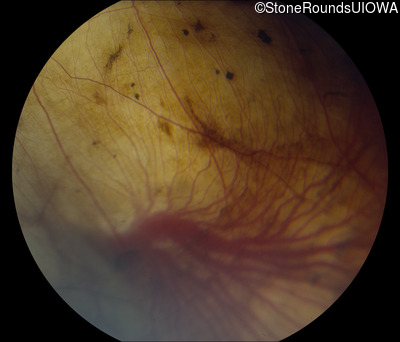

Fundus Photography - Right - 20/40 -2

Exemplar